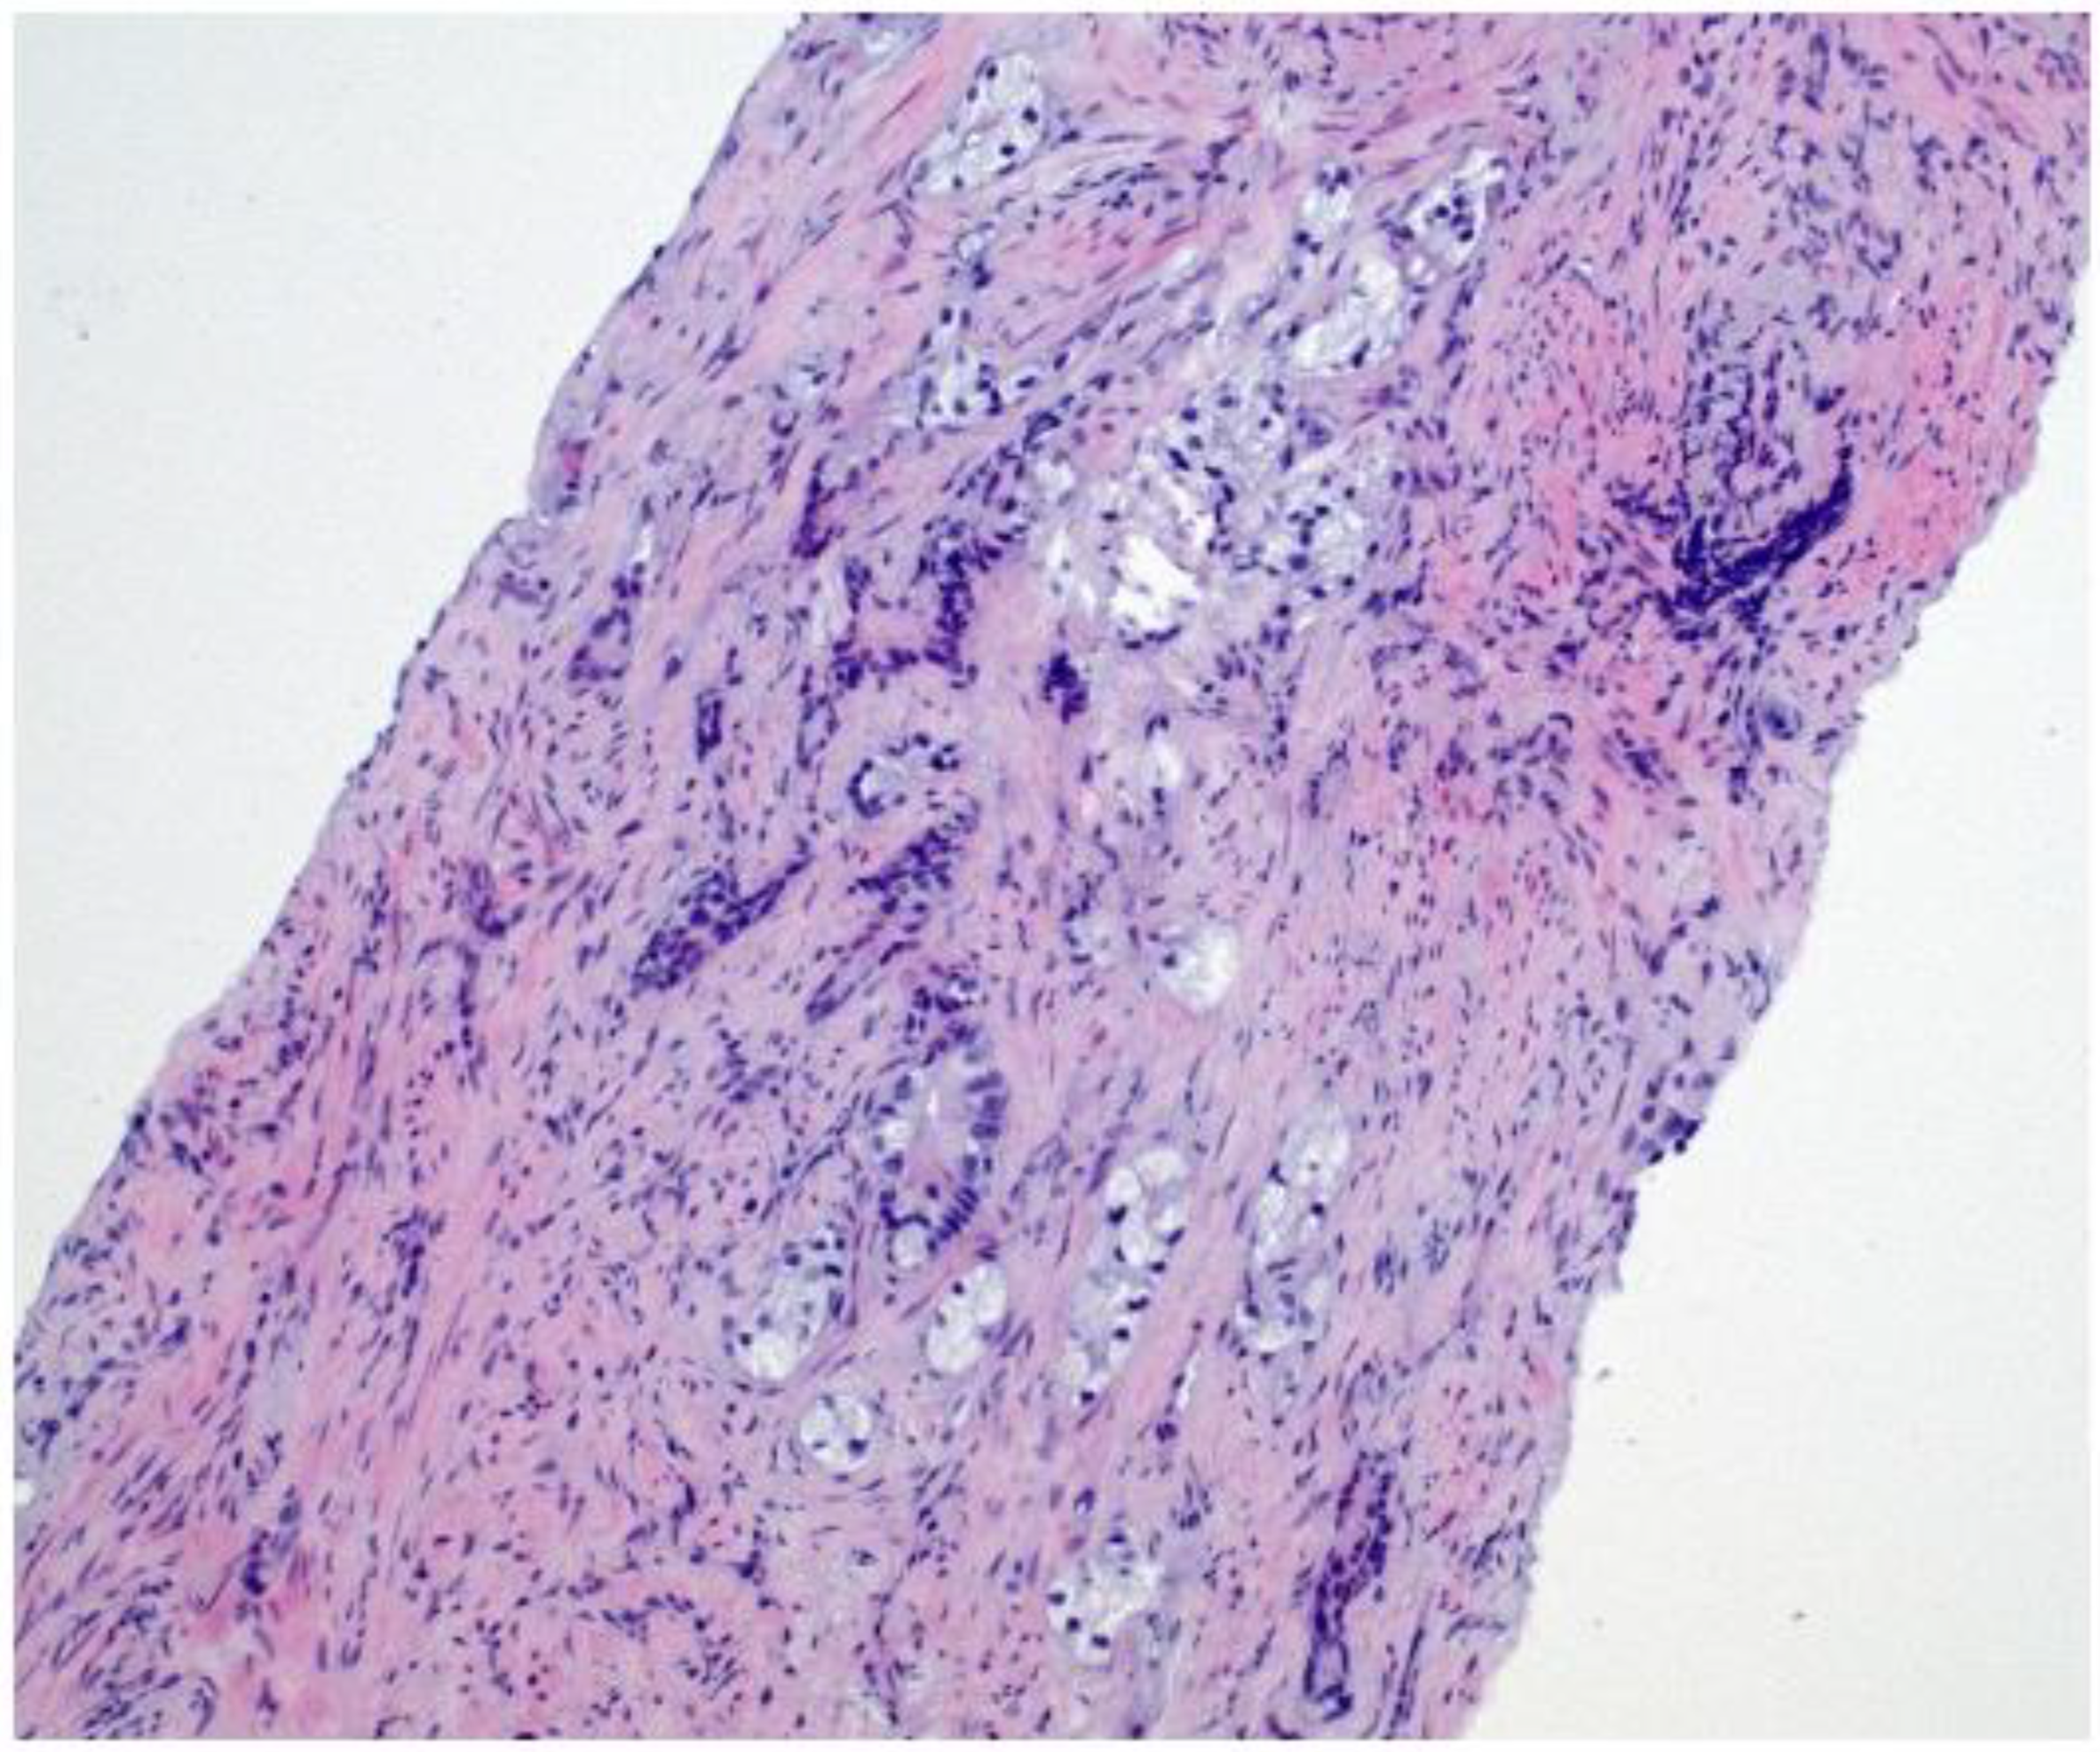

2. Case Presentation

3.3. Role of Immunohistochemistry